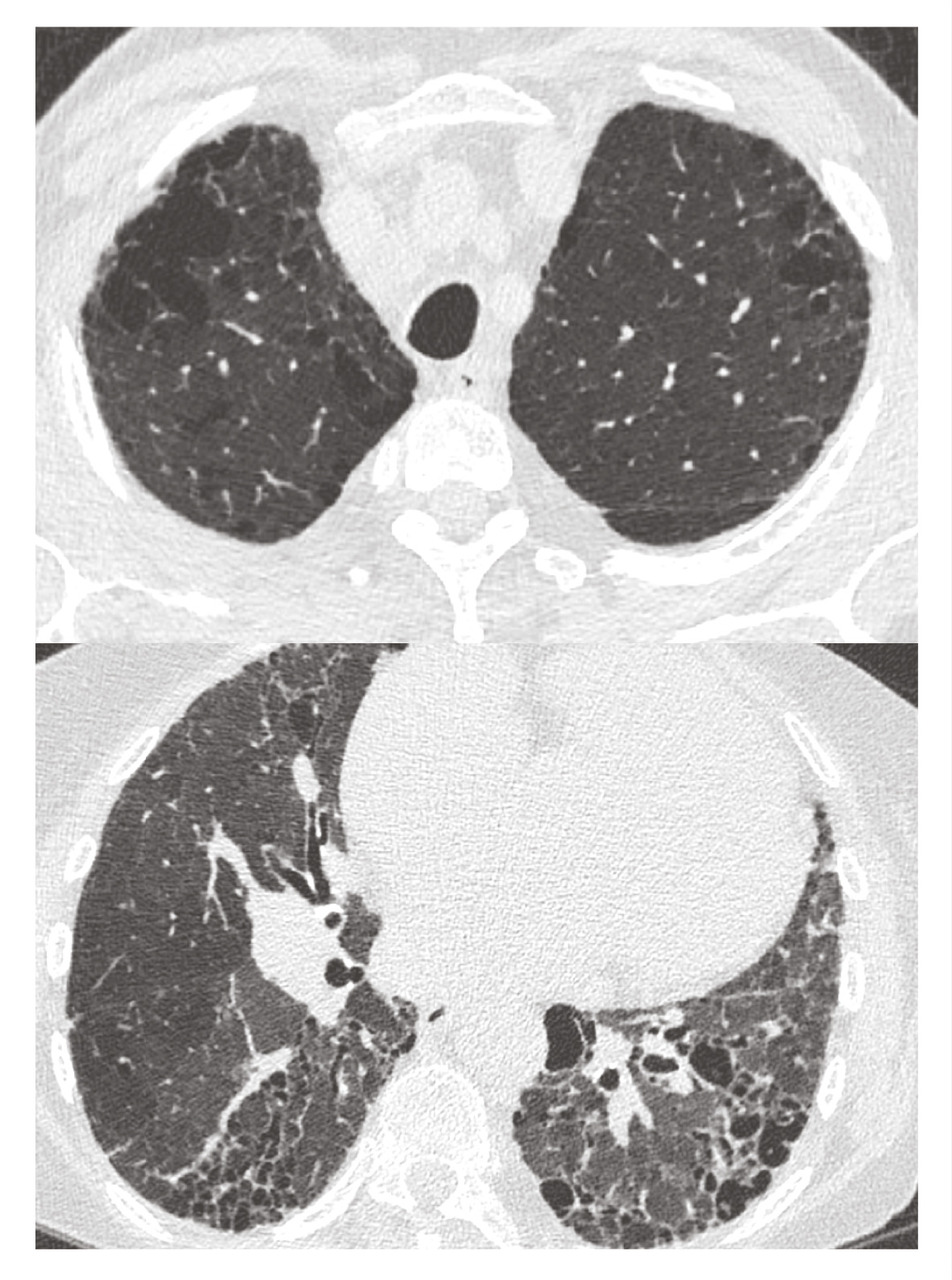

Le syndrome emphysème-fibrose est défini par la coexistence de lésions d’emphysème aux sommets et d’une fibrose pulmonaire aux bases. La prévalence de l’HTP est particulièrement élevée dans ce contexte (de 15 à 55 % des patients). Cette association comorbide est responsable d’une diminution de la DLCO et d’une hypoxémie sévère de très mauvais pronostic quel que soit le traitement (figure ).